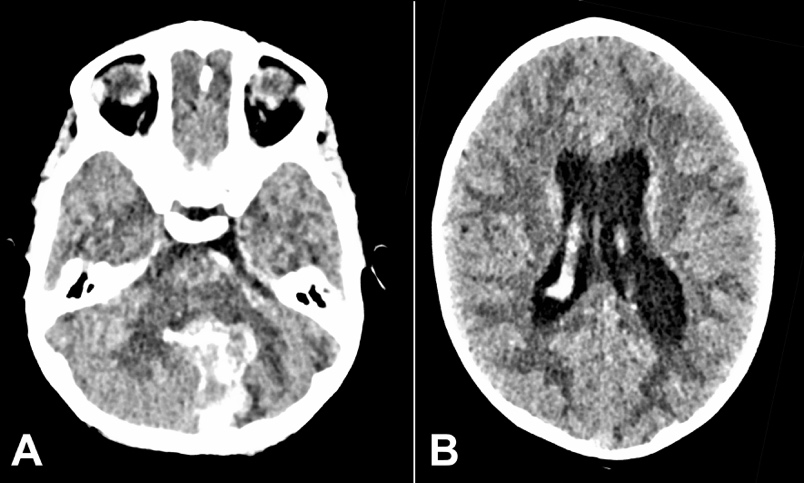

A 4-years-old, previously healthy girl, presented to the emergency department after an episode of drowsiness and unwitnessed fall. Symptoms included headache, vomiting, and fluctuating consciousness levels. Initial GCS with ambulance crew ranged from 10/15-13/15, which deteriorated to 7/15 at hospital presentation. She was intubated/ventilated and an urgent CT head revealed a large hemorrhage into the cerebellar vermis and left cerebellar hemisphere, extending into the ventricular system and causing supratentorial hydrocephalus. (Figures 1A and 1B).

A CT angiogram (CTA) revealed a ruptured aneurysm of the posterior inferior cerebellar artery (PICA) branch. An external ventricular drain (EVD) was inserted for intracranial pressure (ICP) control, and she was admitted to PICU. The aneurysm was coiled, the hematoma evacuated, and a digital subtraction angiography (DSA) revealed an aberrant branch of PICA with a distal aneurysm (Figures 2A and 2B).